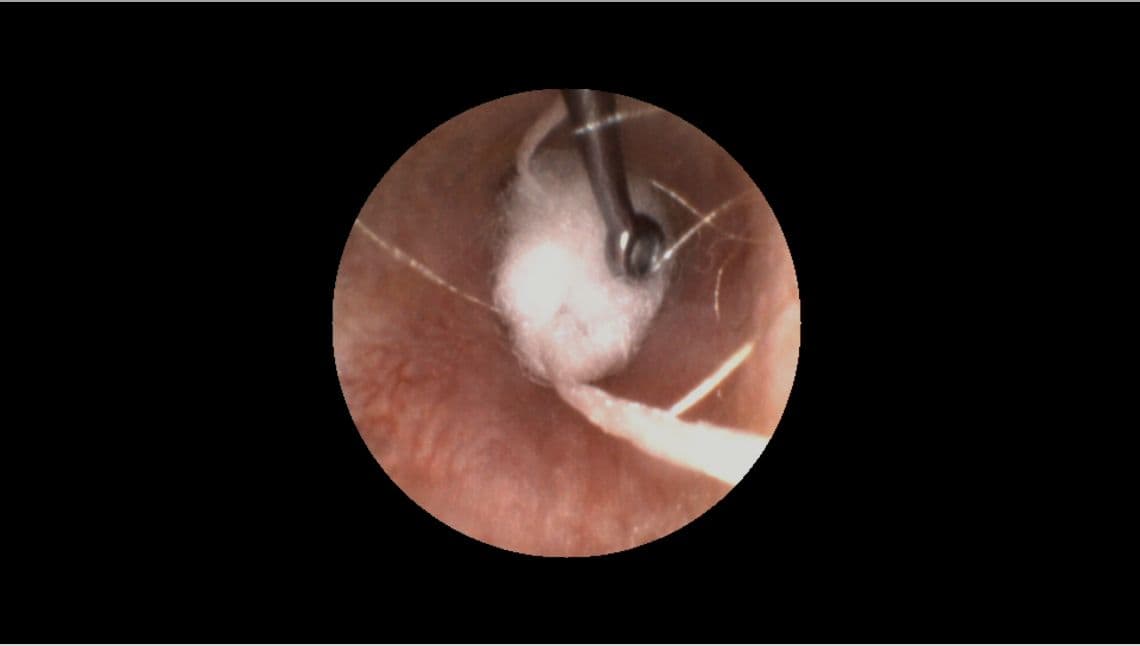

Step 2: Insert the otoblock

The size and type of otoblock you use makes a big difference in the outcome of your impression.

- In most cases, we recommend using cotton, not foam, and flaring it before insertion.

- Properly brace your hand against patient’s head.

- Use your otoscope and a curette to guide the block past the second bend of the ear canal and place it as close as possible to the eardrum.

- Once placed, check your work by inspecting the perimeter of the otoblock with your otoscope to ensure there are no gaps.

Pro Tip: Positioning yourself level to the ear, lifting up the pinna and pulling the tragus forward all help make it easier to see what you’re doing.